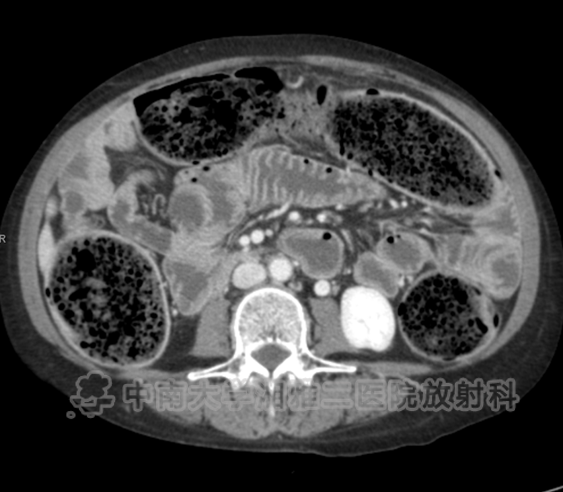

● 在结肠中有明显的粪块残留,在结肠壁(箭头)内存在气体,相关肠壁无增厚或肠系膜脂肪的滞留,与结肠囊样积气一致。